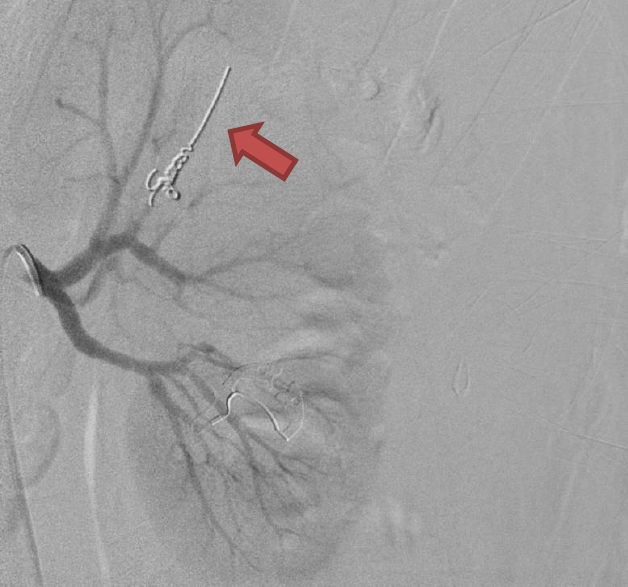

Angioembolisation

Angioembolisation in renal trauma is effective in selected patients.

Trauma CT: Blue arrow is contrast ‘blush’=active bleeding point. Red arrow is perinephric haematoma.

When transferring these patients from smaller hospitals to larger centres, consider whether initial destination should be the ED for rapid re-assessment prior to entering IR suite.